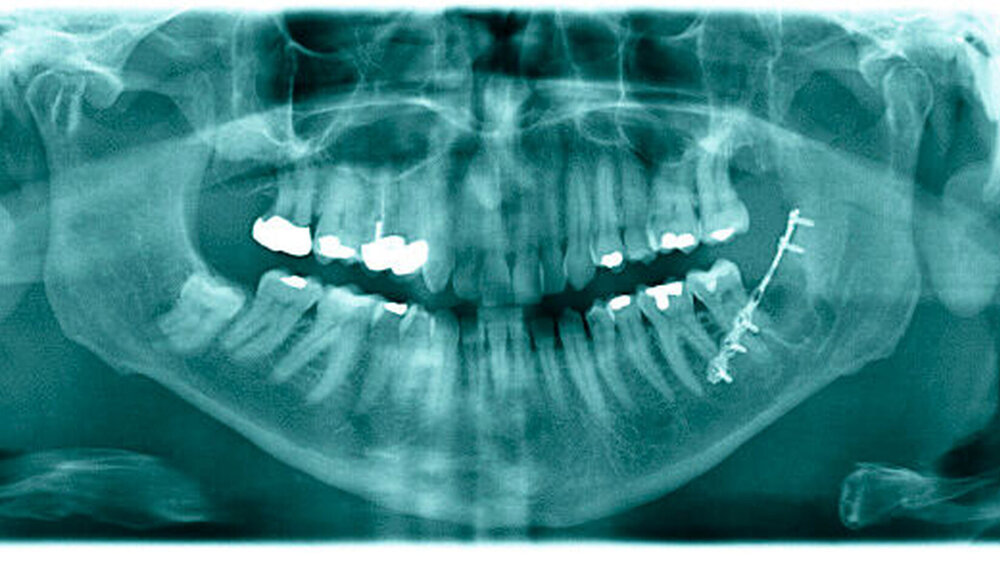

Bei einem 61-jährigen Patienten wurden vor knapp einem Monat die Zähne 28 und 38 osteotomiert. Gut zwei Wochen später bemerkte der Patient ein lautes Knacken beim Biss auf ein Gummibärchen, dessen Entstehungspunkt der Patient auf den Unterkiefer links projizierte. Der Patient wurde erneut beim Hauszahnarzt vorstellig, der in der dann angefertigten Panoramaschichtaufnahme keinen sicheren Frakturausschluss führen konnte (Abbildung 1) und bei weiter bestehenden Schmerzen den Patienten in die Klinik für Mund-, Kiefer- und Gesichtschirurgie nach Mainz überwies.

Im vorliegenden Fall gelang die Darstellung der Fraktur mittels konventioneller Bildgebung, das heißt der Panoramaschichtaufnahme, nicht. Dies liegt an der für die Panoramaschichtaufnahme spezifischen Informationsakquise zur anschließenden optischen Darstellung, bei der durch die tomografische Technik eine bestimmte Schicht im zu untersuchenden Körper im Fokus liegend scharf abgebildet wird. Alle Röhren- beziehungsweise Sensor-näherliegenden Bereiche werden verwischt, so dass auch bereits eine ungeeignete Ausrichtung des Patienten dazu führt, dass die zu untersuchende Struktur nicht mehr im Fokus steht. Dies ist ein typisches Szenario bei stärker dislozierten Frakturen oder auch bei Patienten, die schmerzbedingt nur unzu- reichend gut ausgerichtet werden können. Im beschriebenen Fall war die Fraktur zu fein, als dass sie mit der Panoramaschichtaufnahme hätte abgebildet werden können. Durch die digitale Volumentomografie ist es in der zahnärztlichen Radiologie möglich geworden, in solchen Fällen bereits präoperativ die Diagnose zu stellen. Durch die hohe Auflösung von einer Voxelkantenlänge zwischen 0,1 und 0,4 mm [Spin-Neto et al., 2012] gelingt auch die Darstellung von fissuralen Frakturen. Es werden noch weitaus kleinere Voxelkanten beschrieben, so dass theoretisch eine noch bessere Ortsauflösung möglich wäre, jedoch geht dies mit weitaus längeren Umlauf- und Scanzeiten einher, in denen sich der Patient nicht bewegen darf, so dass dies mit den derzeitigen technischen Lösungen in der Diagnostik am lebenden Objekt unrealistisch ist [Schulze, 2012]. Alternativ zur digitalen Volumentomografie steht die computertomografische Darstellung zur Verfügung, die aus strahlenhygienischen Gründen in vielen derartigen Fällen nicht durchgeführt wird. Mit der digitalen Volumentomografie kann bei Verwendung unterschiedlicher Geräte die interessierende Region, das sogenannte Field of View (FOV), durch die Verwendung unterschiedlicher Zylinder eingegrenzt werden, so dass hier die Option der Dosisreduktion gegeben ist. Der Vollständigkeit halber soll aber auch erwähnt werden, dass es bei der Computertomografie dosisreduzierte Programme gibt, die eine entsprechende Diagnostik zulassen bei Dosiswerten, die auch mit der digitalen Volumentomografie erreicht werden. Daher kann nicht generell behauptet werden, dass Aufnahmen digitaler Volumentomogramme immer eine geringere Dosis haben als entsprechend computer- tomografische Aufnahmen [Ritter et al., 2009]. Eine weitere Option bei Patienten mit derartigen Beschwerdebildern liegt in der Exploration, das heißt der Darstellung des Knochens und der aktiven Suche nach der Fraktur, um dann intraoperativ zu entscheiden, ob es hier zur Frakturierung kam, die gegebenenfalls einer weiteren Therapie bedarf.